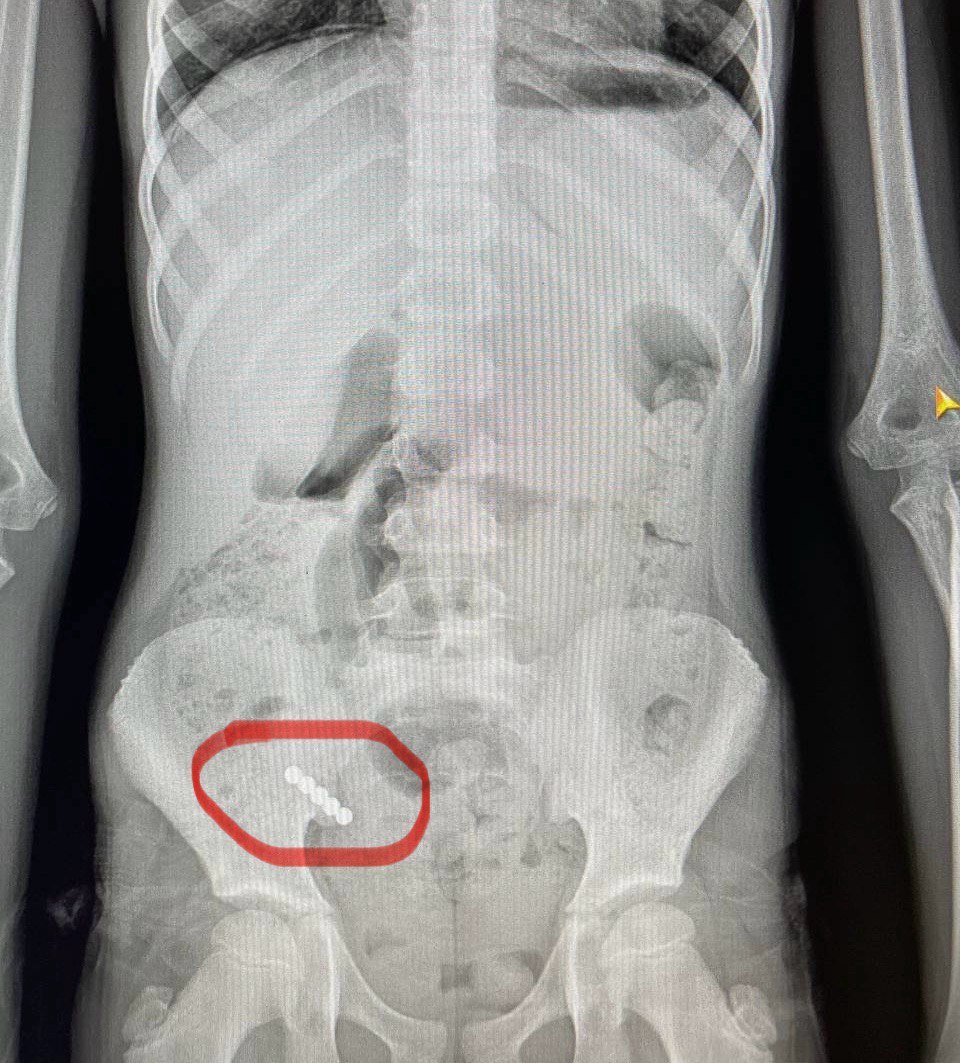

Нещодавно в хірургічному відділенні Волинського обласного медоб’єднання захисту материнства і дитинства на лікуванні перебувала 9-річна дівчинка, яка проковтнула 4 магніти. На жаль, наслідком став перитоніт.

«Водночас, – розповідає хірург дитячий Василь Демчук, – клінічна картина не була типовою для апендициту. Після додаткових обстежень, зокрема рентгенографії, з’ясувалося, що у кишківнику дитини сторонні тіла».

Під час операції лікарі виявили магніти, два з яких склеїлись між собою у різних відділах кишківника. В місці з’єднання утворився пролежень, а згодом – перфорація, внаслідок чого кишковий вміст витік у черевну порожнину.

«Непросто було видалити й магніти. Їх довелося «завести» в апендикс і видалити разом із ним. Дівчинку виписали додому на 10-й день після оперативного втручання», – каже Василь Демчук. Хірург наголошує: найбільшу небезпеку становить проковтування декількох магнітів, адже вони зчеплюються між собою, що й призводить до важких ускладнень.